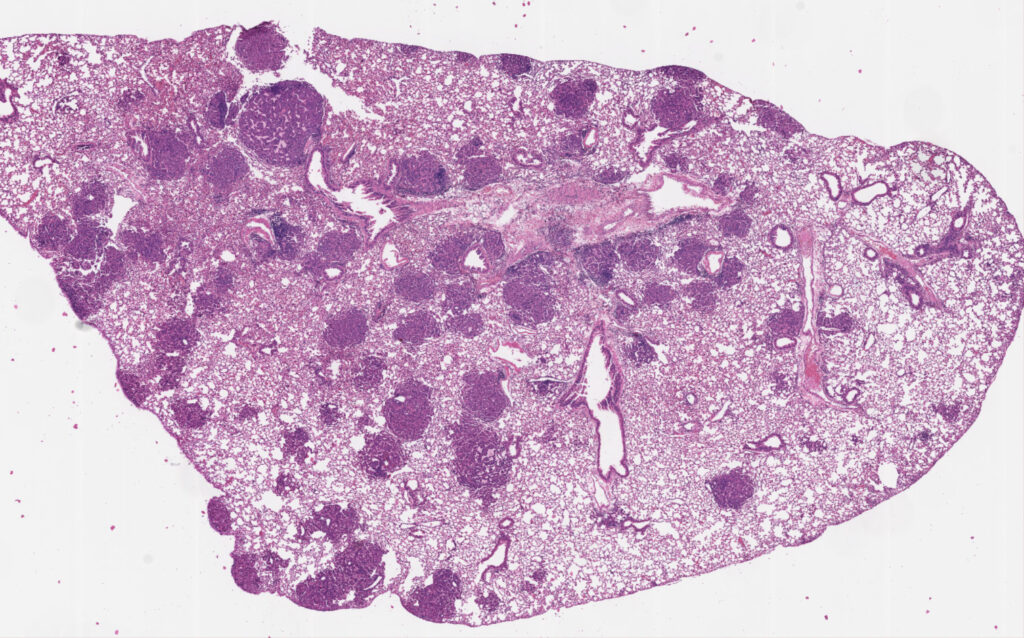

Pictured: H/E stained section of a mouse lung containing several tumor nodules. Image was generated by David Klawon.